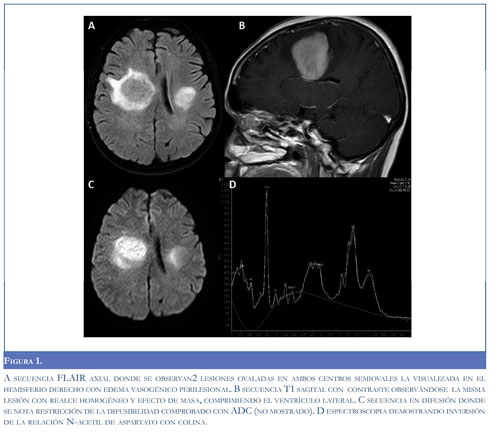

Las lesiones son isodensas o hiperdensas en la TAC (56), en la RM hipointensas en la secuencia de T2 con un patrón de realce homogéneo con la administración de gadolinio (54, 55, 57), también se han descrito hallazgos como el signo de la escotadura en pacientes inmunosuprimidos e inmunocompe-tentes y patrones de realce en anillo incompleto, estos últimos semejan lesiones desmielinizantes, no obstante el anillo en estos es delgado y uniforme, contrario al visto en LPSNC el cual es grueso y no uniforme (55, 58). El edema perilesional es menor al encontrado en otras lesiones tumorales como gliomas o metástasis. En las imágenes de difusión se observa restricción en 90% de los casos antes del tratamiento (59) (Figura 1). En la espectroscopia se observa relación aumentada de colina/creatina y disminuida de N-acetil aspartato/colina así como N-acetil aspartato/creatina (59) (Figura 1).Otros patrones menos frecuentes son calcificaciones, cambios quísticos y realce en anillo (56, 57), este último puede presentarse en pacientes inmunosuprimidos.